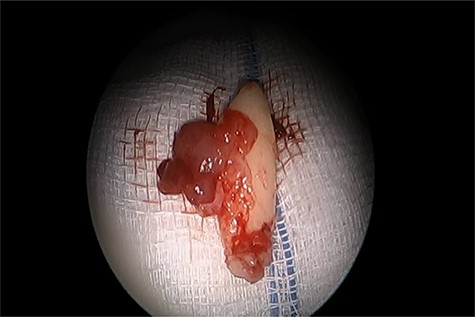

Informed consent was obtained from the parents and the patient underwent endoscopic endonasal enucleation of cyst and removal of ectopic tooth through inferior meatal antrostomy (Figs 2 and 3). Histopathologic examination confirmed the diagnosis of dentigerous cysts.

Inferior meatal antrostomy, after sac enucleation, while removing the tooth.